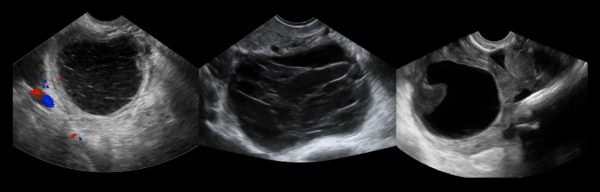

При подозрении на новообразование женщина направляется на УЗИ или лапароскопию.

Чтобы дифференцировать данный недуг от других патологий назначается цветовая допплерография, анализ на онкомаркер СА-125, также приводятся мероприятия, исключающие беременность, включая внематочную.